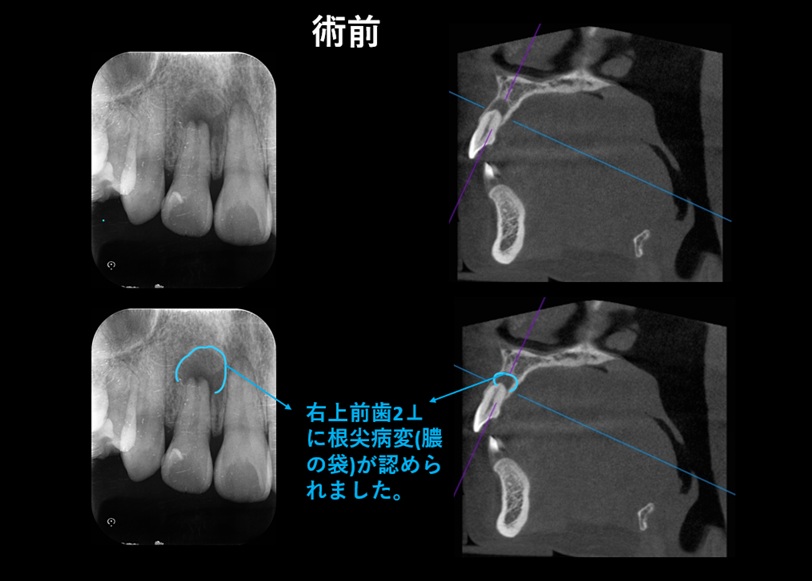

↑ 以前、他の歯科医院で行った詰め物治療の治癒が不完全であったこと、または過去の打撲などが原因となり、右上前歯(右上側切歯)の歯髄(歯の内部の神経)が細菌感染により壊死していました。

その結果、歯の根の先に 根尖病変(膿の袋) が形成されていたため、精密根管治療を行いました。